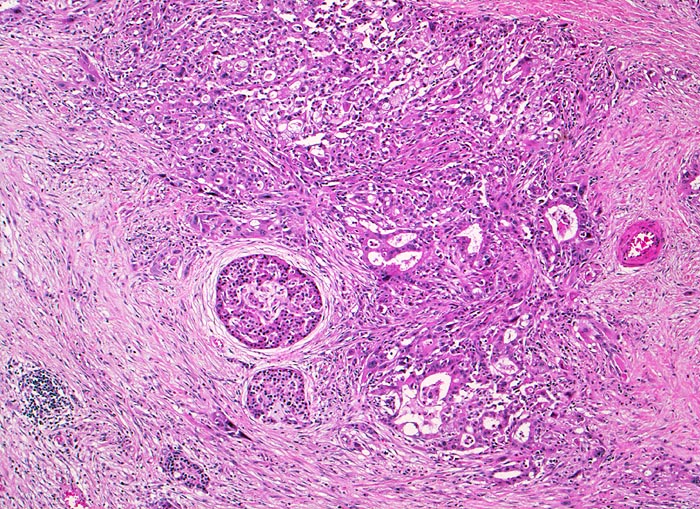

Die meisten Pankreaskarzinome sind mässig bis hoch differenziert und führen zu einer deutlichen desmoplastischen Stromareaktion (derbe Konsistenz). Hochdifferenzierte Tumoren (> 1502) können sehr ähnlich aussehen wie eine chronische Pankreatitis (> 4243). Im Gegensatz zur Pankreatitis sind die neoplastischen Drüsen verformt oder rupturiert und zeigen zelluläre Atypien (grosse polymorphe Kerne mit prominenten Nucleolen). Die Tumordrüsen sind unregelmässig im Stroma angeordnet und nicht lobulär wie in der Pankreatitis. Nicht selten ist eine Nervenscheideninvasion nachweisbar (> 5884). Gelegentlich zeigen die Gänge im tumorfreien Parenchym dysplastische Veränderungen oder der Tumor breitet sich intraduktal entlang des Pankreasganges aus.

• Unregelmässige Anordnung der Drüsen (keine Läppchenarchitektur erkennbar).

• Kribriforme Drüsenformationen.

• Inkomplette Drüsen mit unvollständigen Lumina und Infiltration des Stromas durch Tumoreinzelzellen.

• Nekrotische Tumorzellen in den Drüsenlumina.

• Ausgeprägte Polymorphie und Hyperchromasie der Tumorzellkerne.

• Desmoplastisches Stroma.

• Rechts oben Reste von nicht neoplastischem Pankreasparenchym mit fokaler chronisch obstruktiver Pankreatitis als Folge von tumorbedingten Gangobstruktionen: Vollständige Atrophie des exokrinen Pankreas bei erhaltenen Inseln. Ersatz des atrophen Parenchyms durch Fibrose. Chronisches Entzündungsinfiltrat.